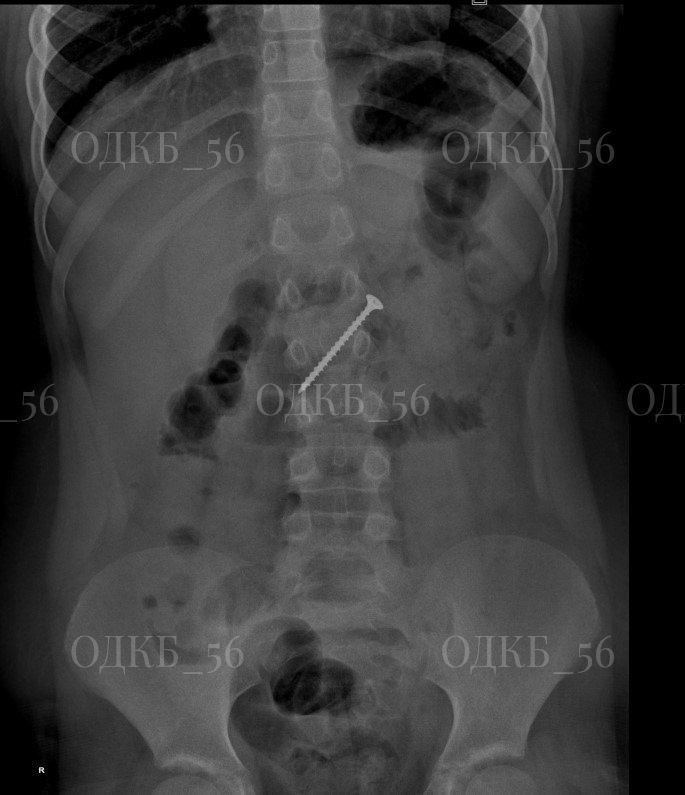

🤯5-сантиметровый саморез проглотил ребенок в Оренбурге

В Оренбургской областной детской больнице спасли ребенка, проглотившего 5-сантиметровый саморез. Мальчик 9 лет был экстренно доставлен из района, и рентген подтвердил опасения родителей.

В ходе срочной эндоскопии врачи обнаружили, что саморез переместился в двенадцатиперстную кишку, что создавало угрозу жизни.

Медики успешно извлекли опасный предмет. Состояние ребенка стабилизировали, и его выписали домой.